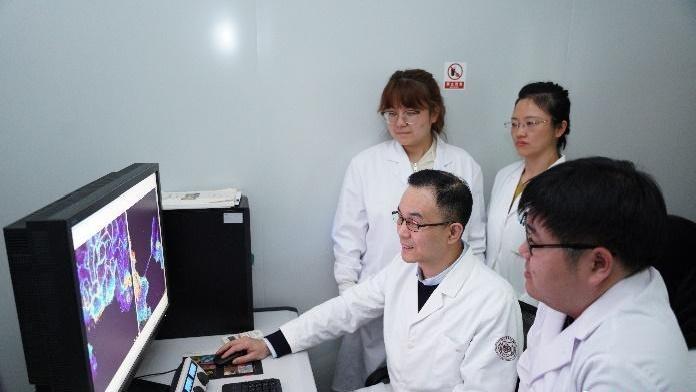

北大新突破:一滴血 查清病从哪来

最近,北京大学何爱彬团队联合多方合作者在国际权威期刊发表最新研究成果。 他们研发出具有自主知识产权的新一代表观液体活检技术cf-EpiTracing,实现仅靠少量血浆样本,就能精准识别病变来源组织、发现早期病2026-03-09 -